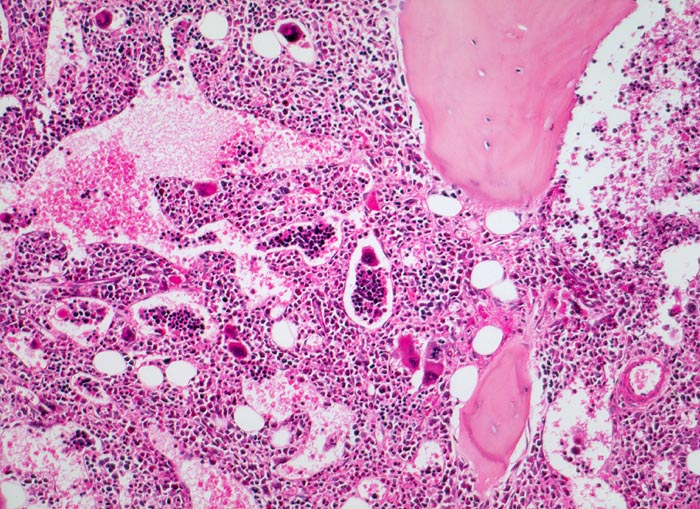

PathoPic – image database / PathoPic ID 3913 - Primäre Myelofibrose (PMF)

Primäre Myelofibrose (PMF)

Knochenmark, Beckenkamm

Hyperplastisches Mark mit fast vollständiger Verdrängung des Fettmarks. Typisch ist der Nachweis von Blutbildungsherden und Megakaryozyten in erweiterten Marksinus.

Splenomegalie, leichte Anämie, Leukozytose und Thrombozytose festgestellt bei einer Routineuntersuchung bei asymptomatischer Patientin.

Histologie

100